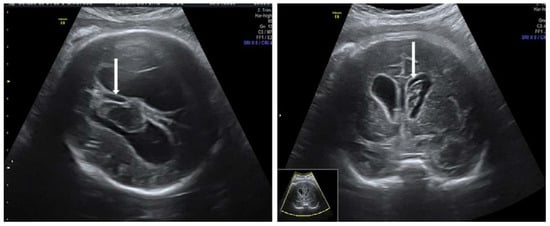

3.3. Primary Autoimmune Thrombocytopenia—ITP Antibodies

- Wainwright, B.; Bhan, R.; Trad, C.; Cohen, R.; Saxena, A.; Buyon, J.; Izmirly, P. Autoimmune-mediated congenital heart block. Best Pract. Res. Clin. Obstet. Gynaecol. 2019, 64, 41–51. [Google Scholar] [CrossRef]

- Brito-Zerón, P.; Izmirly, P.M.; Ramos-Casals, M.; Buyon, J.P.; Khamashta, M. The clinical spectrum of autoimmune congenital heart block. Nat. Rev. Rheumatol. 2015, 11, 301–312. [Google Scholar] [CrossRef] [PubMed]

- Eliasson, H.; Sonesson, S.E.; Sharland, G.; Granath, F.; Simpson, J.M.; Carvalho, J.S.; Jicinska, H.; Tomek, V.; Dangel, J.; Zielinsky, P.; et al. Isolated atrioventricular block in the fetus: A retrospective, multinational, multicenter study of 175 patients. Circulation 2011, 124, 1919–1926. [Google Scholar] [CrossRef]

- Popescu, M.R.; Dudu, A.; Jurcut, C.; Ciobanu, A.M.; Zagrean, A.-M.; Panaitescu, A.M. A Broader Perspective on Anti-Ro Antibodies and Their Fetal Consequences—A Case Report and Literature Review. Diagnostics 2020, 10, 478. [Google Scholar] [CrossRef]